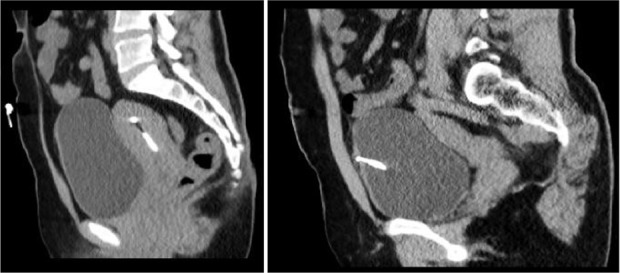

Case presentation: Our case was a 41-year-old woman whose IUD was accidentally discovered in her bladder during a routine ultrasound. The IUD has migrated from its normal position in the uterus to the bladder. The IUD was successfully removed by cystoscopy without any complications.